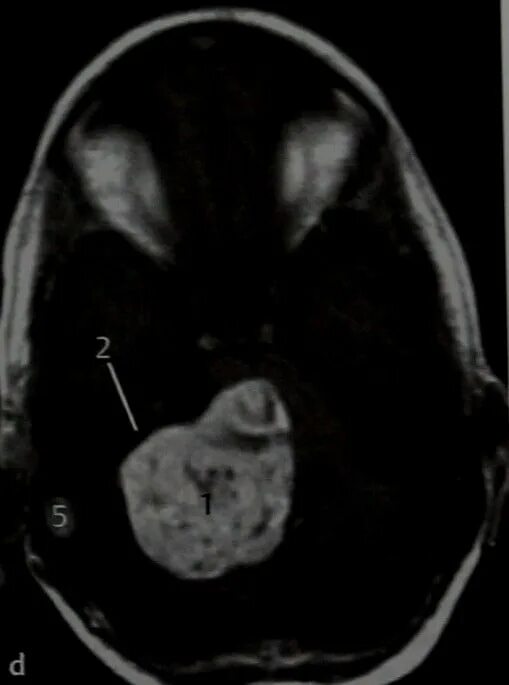

Мрт головного мозга мосто мозжечкового угла